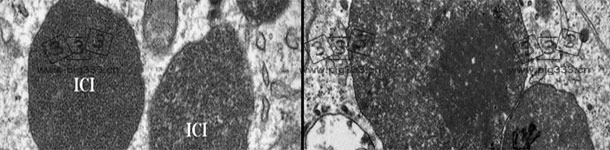

PCV2-SD病猪的淋巴结电镜图. PCV2胞浆内包含体。病毒粒子呈亚晶状排列(见右图中小插图)。图片由卡罗莱纳州Rodríguez-Cariño提供。